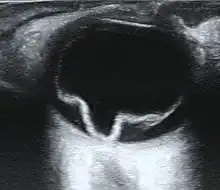

Ultrasound of a retinal detachment in a patient presenting with complete vision loss and light perception only.

Ultrasound, MRI, and CT scan are commonly used to diagnose retinal detachment.